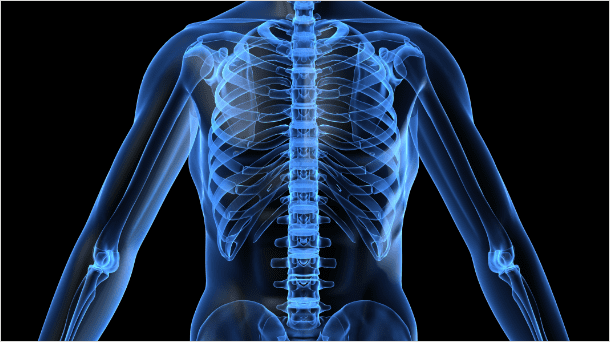

정상

비정상